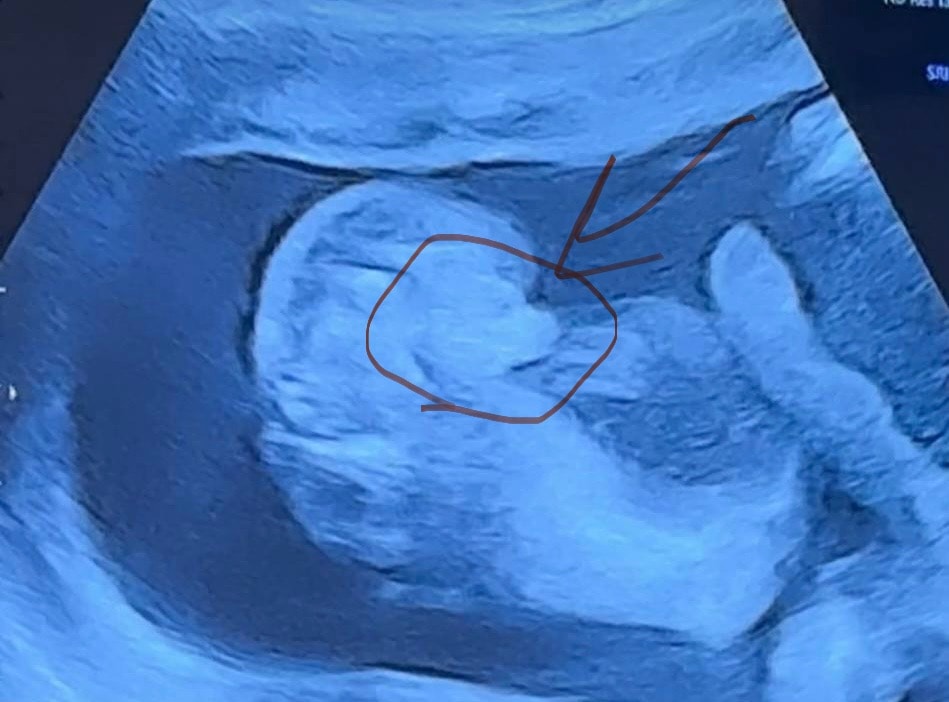

я вижу девочку

Девочка

Ия, извините но бывает ли такие большие половых губ?)))

Zaynab, они все очень сильно отекшие. Девочка у вас.

Zaynab, да, у новорожденных они такие

Вам в 36 недель не смогли точно сказать пол? Вроде девочка..

Мальчик или девочка? Малышка или малыш 👶